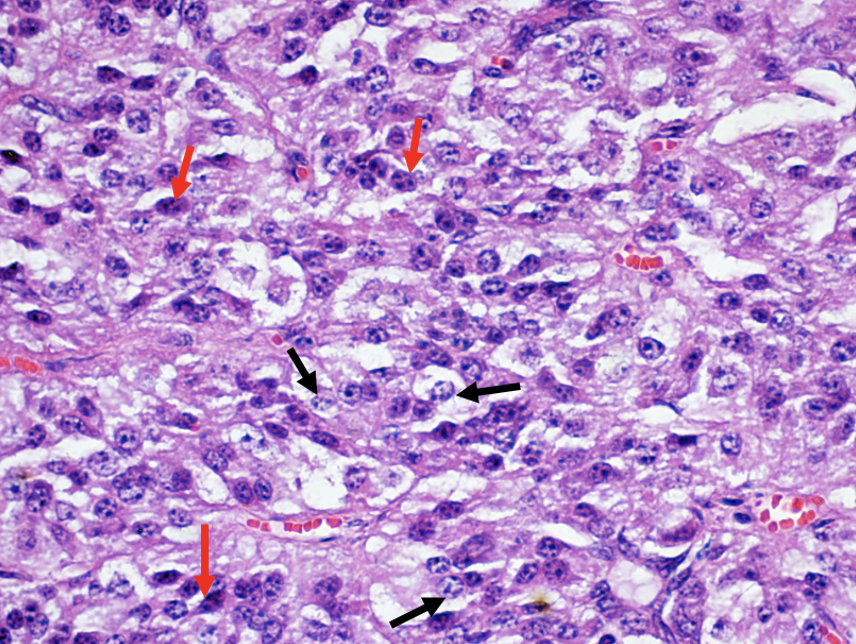

Chromophobes –> black arrows

Acidophils –> brown arrows

Basophils –> red arrows

Red arrow –> follicular cells

Black cells –> C cells

Black arrows –> Chief cells

Black arrows –> oxyphil cells

Blue arrows –> chief cells